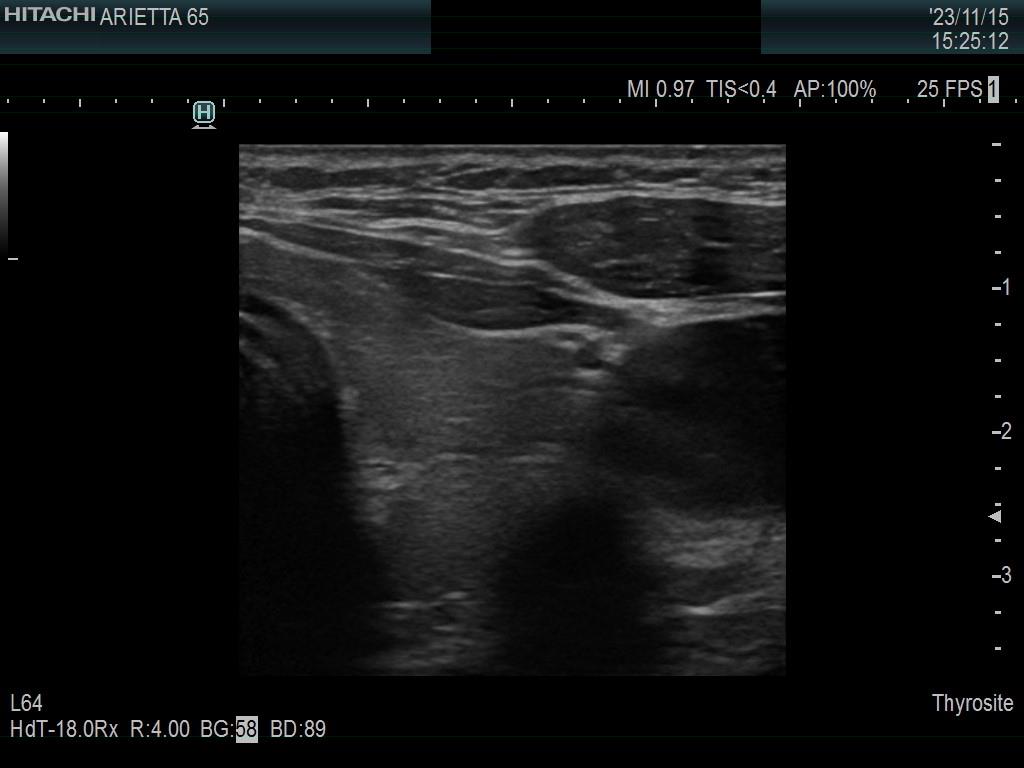

Ultrasonography. The thyroid was minimally hypoechoic. The echogenicity of the dorsal part of the left lobe where the nodule was previously described did not differ from other parts of the thyroid. There was a connective tissue running ventral to this part of the lobe and hypoechoic areas were found upper and dorsal to this. Neither halo nor perinodular blood flow was present.

The area in question did not correspond to a pathological nodule. It seemed to be circumscribed because of the presence of connective tissue and thyroid vessels.

A follicular tumor must have a capsule which ultrasound sign, either a complete halo and/or perinodular blood flow are present in more than 95% of cases. Both features were absent in this case.